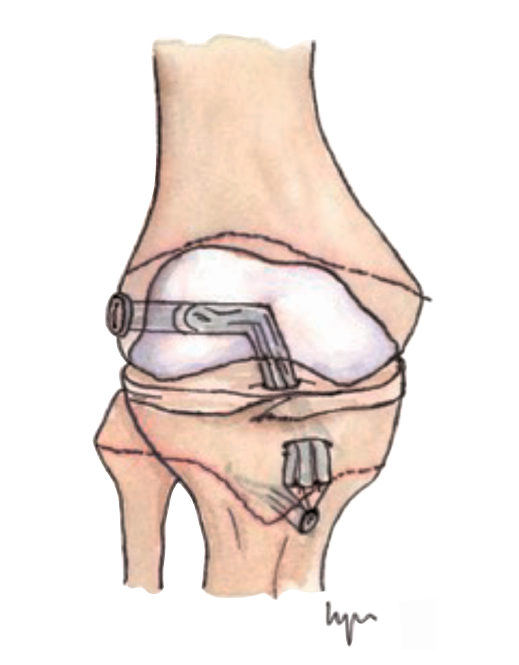

Figura 4. Técnica transepifisaria o todo epifisaria.

Otra de las técnicas de ahorro fisario es la llamada all epiphyseal. La primera de estas técnicas fue descrita por Anderson(13)(Figura 4) y está indicada en pacientes en estadio de Tanner I, II o III. Se realiza evitando la invasión de la fisis por parte de los túneles, utilizando injerto cuadrifascicular de isquiotibiales, que son estabilizados en el fémur mediante un sistema de tenosuspensión cortical y en la tibia con un tornillo interferencial distal a la fisis (Figura 5). Los resultados en un grupo de 12 pacientes fueron buenos, pero refieren que la técnica es compleja y demandante para un cirujano no experto en rodilla. Esta técnica minimiza el daño fisario, es anatómica y reproduce la isométrica(71). Se ha descrito la aparición de una deformidad angular relacionada con una epifisiodesis secundaria por sobretensionado de la plastia. En la actualidad, se han descrito multitud de modificaciones de esta técnica(15,72,73,74)(Figura 6).